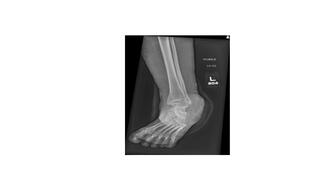

As concepts surrounding minimally invasive bunion surgery continue to evolve and improve, many have found the need to add these surgical techniques to their current skill set. This article aims to briefly review the current concepts of MIS...